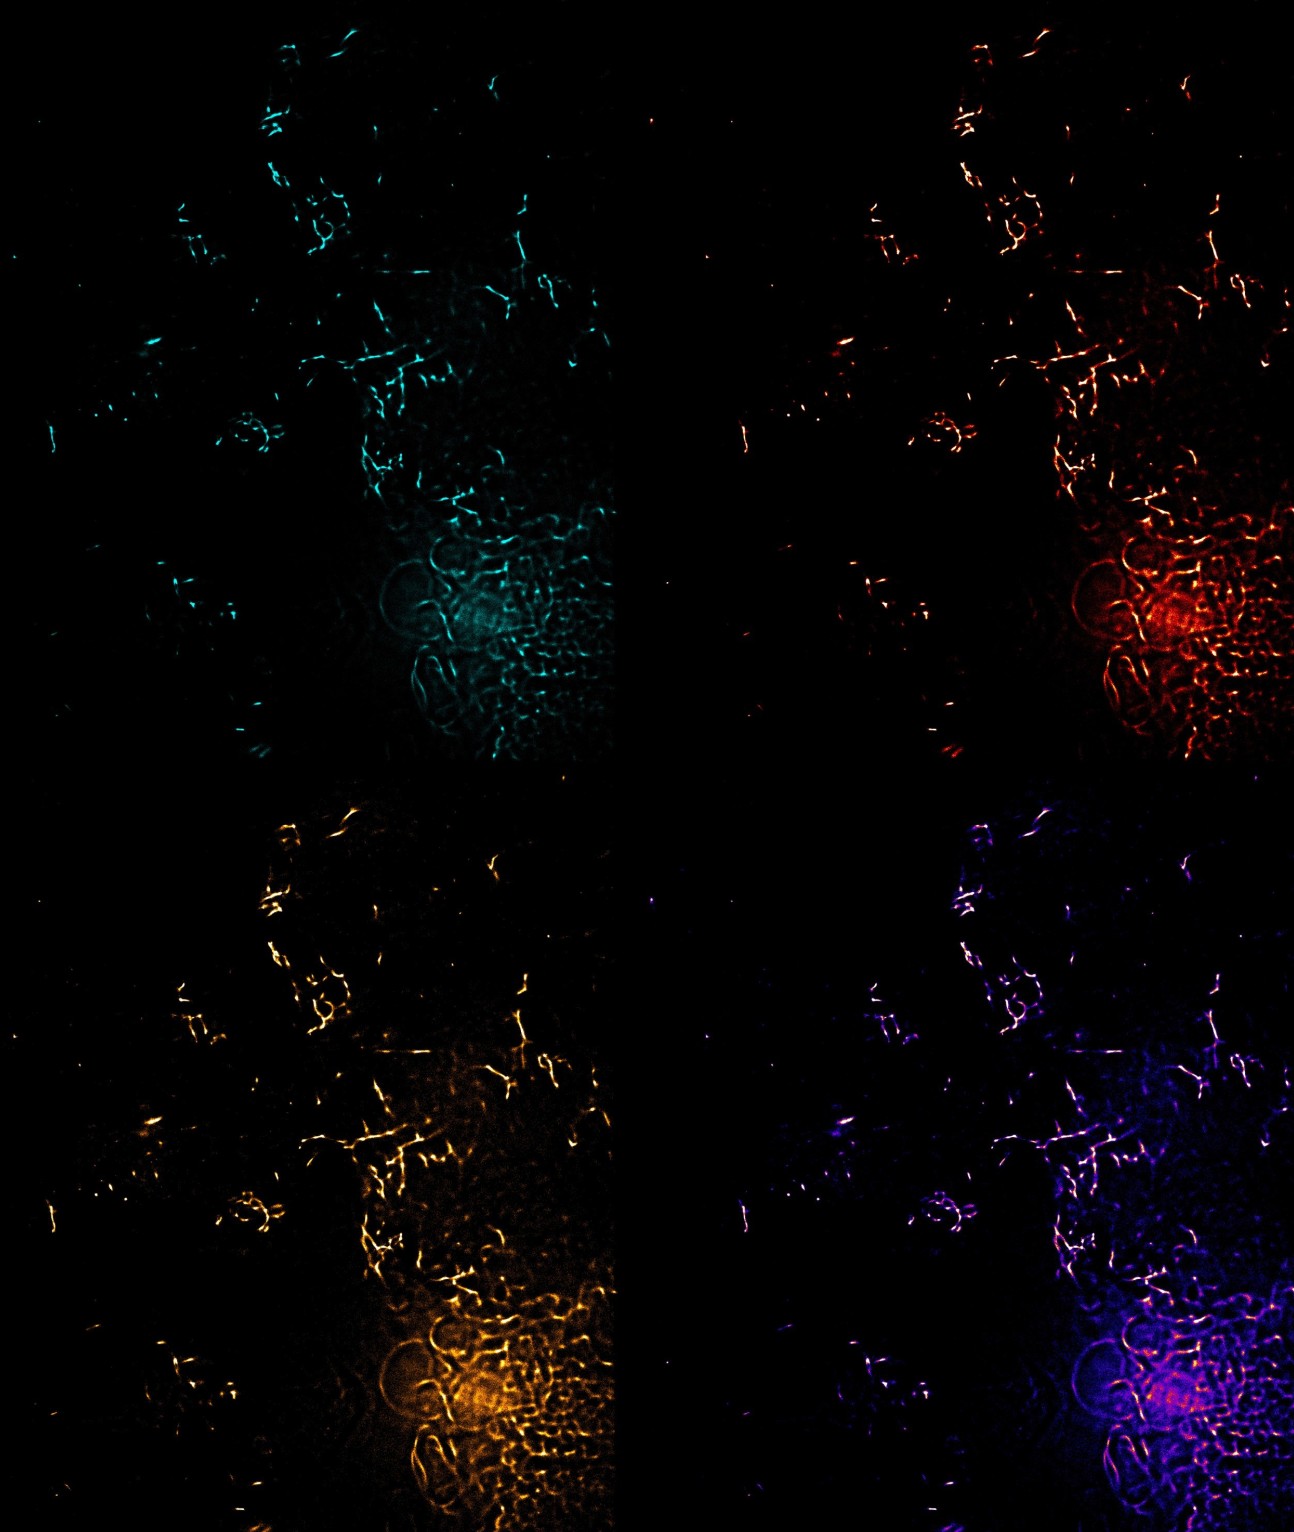

Amyloid Warhol - Huzefa Rupawala (Ye lab)

"This artwork is inspired by the famous artist, Andy Worhol.

This work is entitled 'Amyloid Worhol'. The image depicts a multicolour super-resolved amyloid-beta plaque from the App-NL-G-F triple knock-in mouse model."